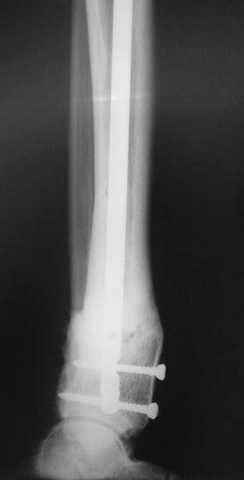

5, 6 - через 2,5 мес после травмы выполнен закрытый остеосинтез блокируемым штифтом.

7, 8, 9, 10, 11 - через 8 мес после травмы перелом сросся.